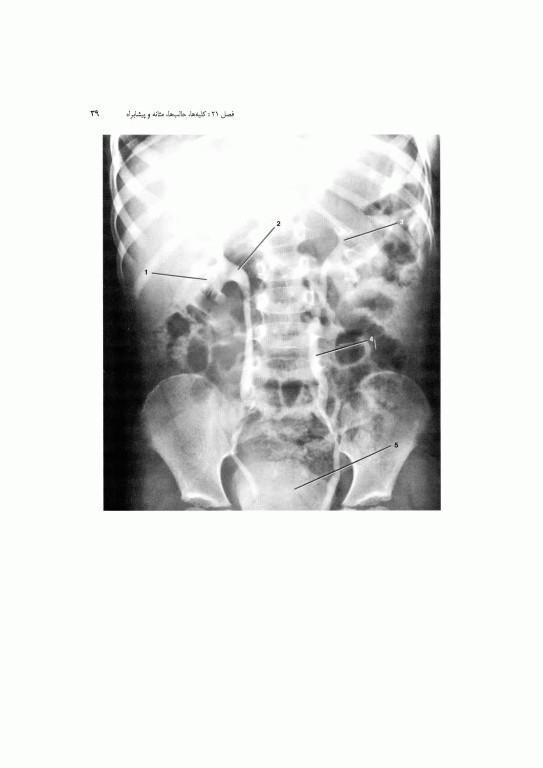

1. آناتومی بالینی: پایه این بخش اطلاعات پایه سودمندی را برای کمک به پزشک در تشخیص و طراحی درمان ارائه مینماید. نمونه‌های متعدد رادیو گرافهای نرمال، CT اسکن، MRI و سونوگرامهای مربوطه نیز نشان داده شده است. همچنین، تصاویری از آناتومی مقطع عرضی آورده شده است تا دانشجو با تجسم آناتومی سه بعدی آشنا شود که این امر در تفسیر کلیشه‌ها بسیار مهم است.